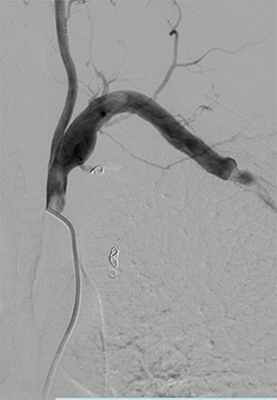

Контрольная МСКТ от 08.06: состояние после резекции аневризмы правой ОПА и ОБА с линейным аортобедренным протезированием. Анастомозы аортобедренного шунта состоятельны; данных, свидетельствующих об экстравазации контрастного вещества, не получено. Тромбирование аневризмы правой ОПА и ОБА. Удовлетворительное, гомогенное контрастирование протезов подколенных артерий (рис. 4). Рисунок 4. Мультиспиральные компьютерные томограммы аорты и артерий нижних конечностей после операций. а - контрастируется остаточная полость аневризмы подвздошной артерии справа. Рисунок 4. Мультиспиральные компьютерные томограммы аорты и артерий нижних конечностей после операций. б - гомогенное контрастирование протезов подколенных артерий.